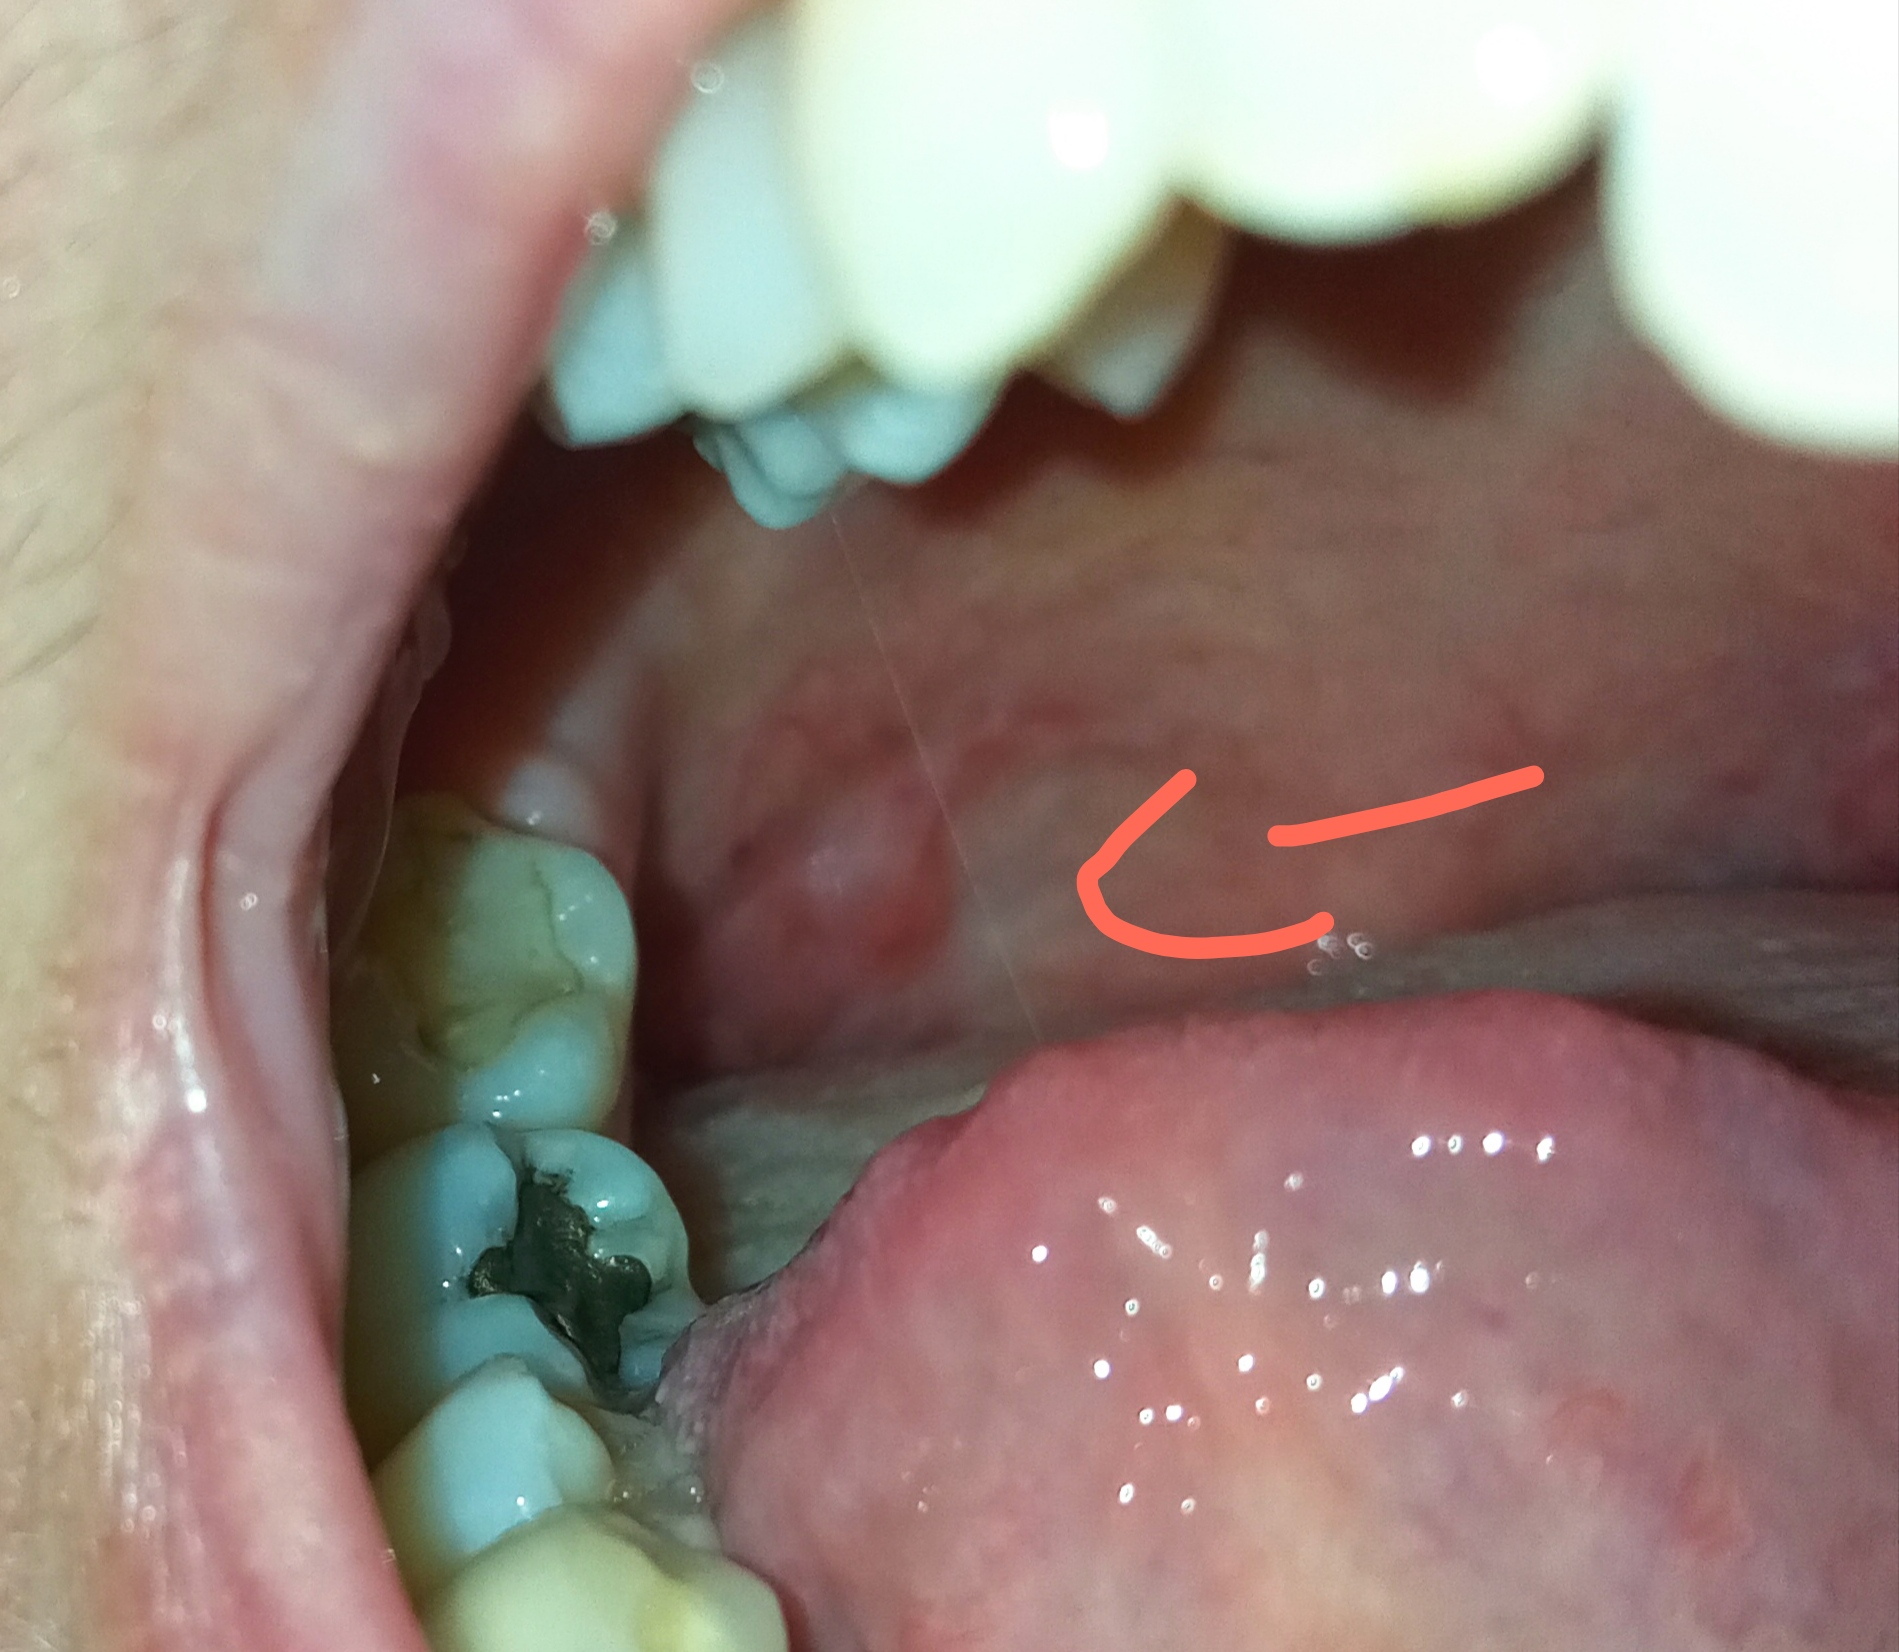

Buongiorno, da qualche giorno ho notato questa formazione sul palato molle. Non è dolorante, me ne sono accorta per caso. L'ha vista il mio medico di base, dice che il palato molle è infiammato, la parte opposta per es si presenta molto rossa. Non fumo e non bevo alcolici. Soffro di reflusso gastroesofageo. Ho la cattiva abitudine di bere bevande bollenti. Ricordo di aver deglutito qualcosa di estremamente bollente e aver sentito proprio dolore in quella zona, però non so quantificare quanto tempo fa. Cosa potrebbe essere? Su internet non ho trovato nulla che gli somigli. Grazie.

Sig. Sandra, se il tutto regredisce spontaneamente in 15 giorni non è nulla di preoccupante.